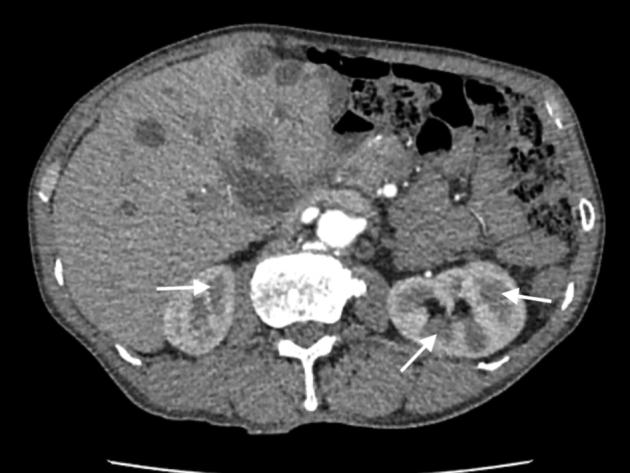

A Case of Hepatic Cyst-Induced Internal Jugular Venous Thrombosis.

• Echocardiography can demonstrate hepatic cyst–induced right atrial compression. • Hepatic cyst–induced blood flow stasis can cause internal jugular venous thrombus. • Laparoscopic deroofing of hepatic cysts is a safe and effective treatment.

• 肝囊肿所致的血流淤滞可导致颈内静脉血栓形成。

• 腹腔镜下肝囊肿去顶术是一种安全有效的治疗方法。